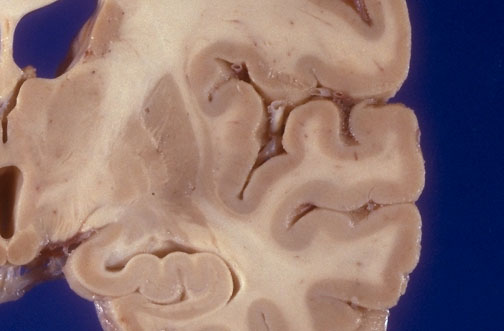

| Identify the following regions of a normal coronal section of magnified cerebrumin the image above: Anterior Commissure - Anterior Nucleus of Thalamus - Body of Caudate Nucleus - Claustrum - Dorsal Medial Nucleus of Thalamus - External Capsule - Extreme Capsule - Globus Palidus I - Globus Palidus II - Hippocampus - Inferior Temporal Gyrus - Insular Cortex - Internal Capsule - Lateral Ventricle - Mammillary Body - Middle Cerebral Artery - Middle Temporal Gyrus - Third Ventricle - Optic Tract - Putamen - Superior Temporal Gyrus - Ventral Lateral Nucleus of Thalamus |